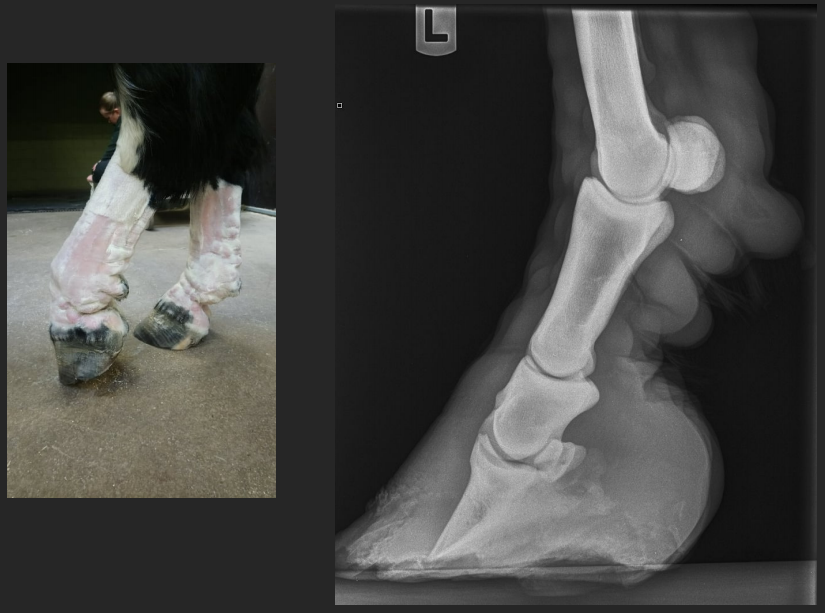

is a degenerative condition affecting the pastern or coffin joints of horses. It is a form of osteoarthritis that results in the abnormal growth of bone around these joints. Ringbone is categorized as either high ringbone or low.